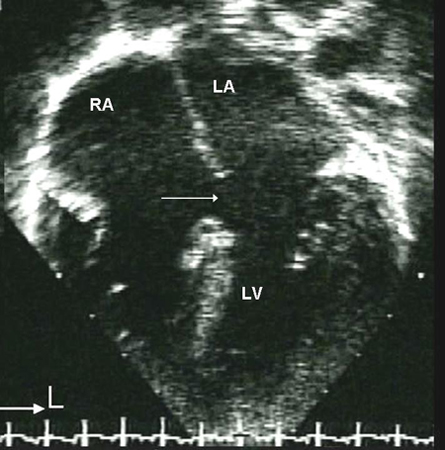

Imagem da ecografia apical de 4 câmaras de um defeito do septo atrial (DSA) do ostium primum (seta). (AD) átrio direito; (AE) átrio esquerdo; (VE) ventrículo esquerdo

Imagem cedida por Patrick W. O'Leary, MD